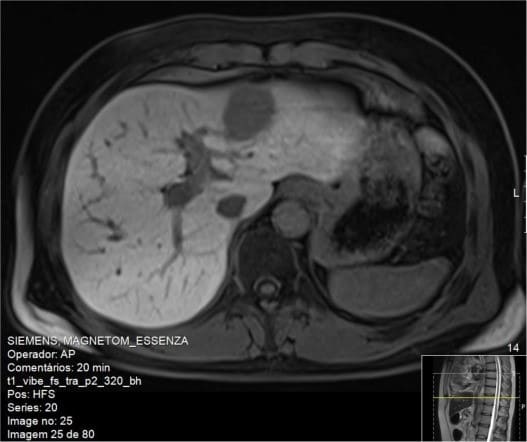

Пациентом 1 был 52-летний мужчина с умеренным потреблением алкоголя в анамнезе, ранее употреблявший наркотические средства внутривенным путем, имеющий факторы риска болезней системы кровообращения (сахарный диабет 2 типа, артериальная гипертензия и дислипидемия) и хроническим ВГС (генотип 3а), диагностированным в 1997 году. Осложнениями ВГС являлись вторичный гемохроматоз и пролиферативный мембранозный гломерулонефрит. Эластография печени показала значения, соответствующие степени фиброза печени F4 по шкале METAVIR. В 2011 году он завершил 24-недельную терапию пегилированным интерфероном и рибавирином и продемонстрировал быстрый вирусологический ответ. Тем не менее, во время последующего наблюдения биохимические данные говорили о процессах цитолиза. Приблизительно через три месяца после окончания терапии подтвердилась её неэффективность. В период с апреля по октябрь 2015 года данный пациент прошел 24 недельный курс лечения ледиспавиром, софосбувиром и рибавирином, достигнув устойчивого вирусологического ответа. Спустя 24 недели после окончания терапии ВГС не определялся, но при прохождении планового УЗИ брюшной полости было выявлено гетерогенное узловое образование в левой доле 43 на 32 мм. Это образование отсутствовало на УЗИ выполненном до начала лечения. Дополнительная магнитно-резонансная томография позволила предположить аденому печени (рис. 1), но биопсия печени показала наличие гепатоцеллюлярной карциномы. В то время уровень альфа-фетопротеина в сыворотке крови составлял 204,20 МЕ / мл. Пациент был подвергнут 2/3 бисегментэктомии. Гистологическое исследование выявило наличие хорошо дифференцированной гепатоцеллюлярной карциномы с признаками лимфатососудистой инвазии на расстоянии 3 мм от операционного края (pT2NxR0).